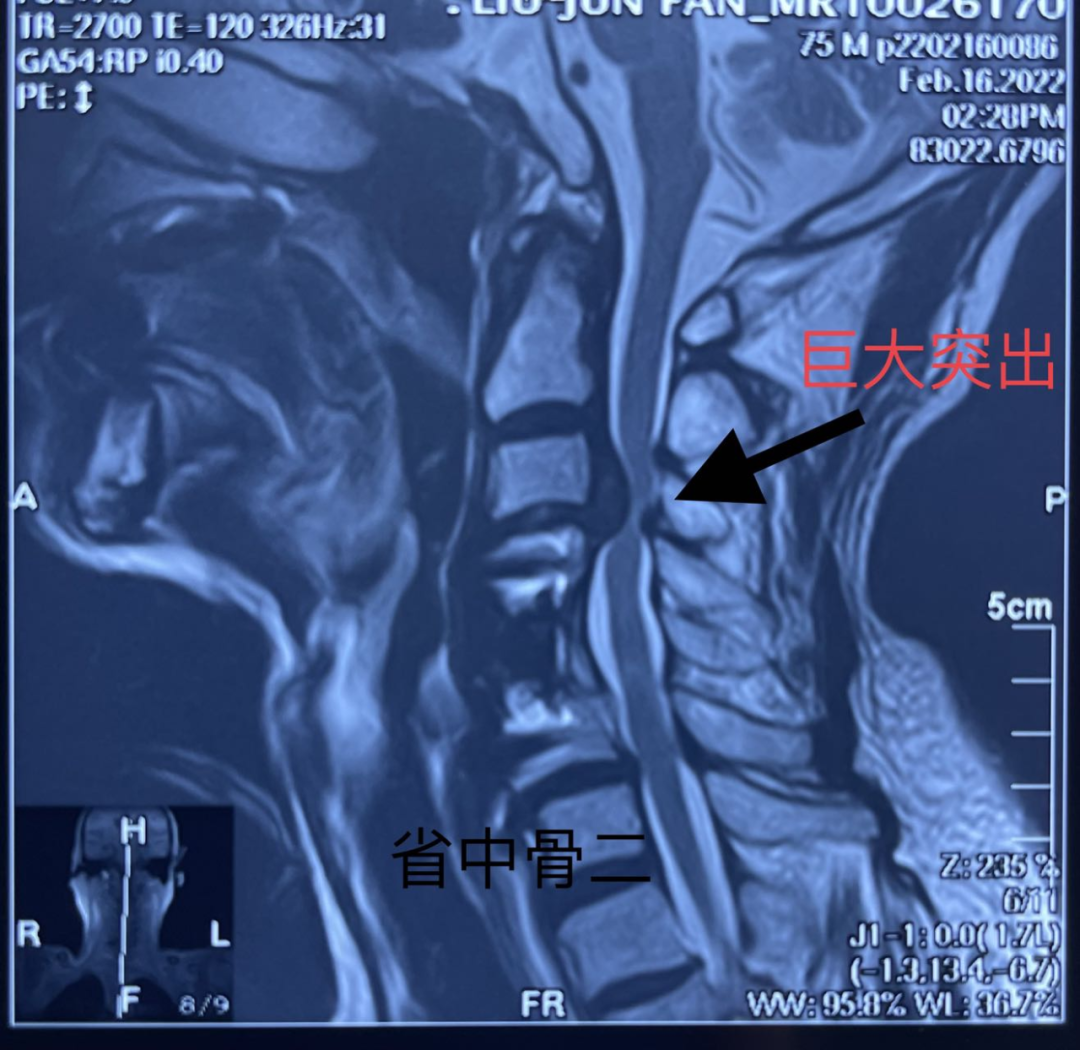

查颈椎核磁共振后,原先手术的临近节段颈3/4出现问题,突出巨大,压迫神经。因患者经历过一次颈椎手术,再次手术难度加大,患者进行了长达一年的保守治疗,但始终效果不明显。

患者辗转来省中医院就诊于全健主任,明确诊断后,目前患者的确有手术指征,而且潜在风险较大,建议患者还是进行手术治疗。接诊入院后骨伤二科脊柱团队对患者进行了详细的检查和评估,王彦鹏副主任医师了解患者目前的情况后,经过一系列的术前讨论,决定在不触动患者原有融合的基础上,用经典的颈椎ACDF(颈椎间盘切除并椎间植骨融合手术)进行翻修。

经过综合考量,最终给患者采取全麻下颈椎ACDF手术,手术当中取出患者原有的前路钛板,对颈3/4椎间盘进行切除后,取出压迫的髓核组织,植入融合器,并将原有的钛板进行加长固定。